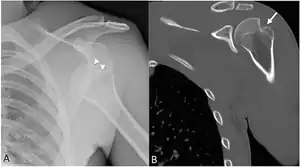

| Anterior shoulder dislocation on X-ray with a large Hill–Sachs lesion | |

A Hill–Sachs lesion, or Hill–Sachs fracture, is a cortical depression in the posterolateral head of the humerus. It results from forceful impaction of the humeral head against the anteroinferior glenoid rim when the shoulder is dislocated anteriorly.

X-ray at left shows anterior dislocation in a young man after trying to get up from his bed. X-ray at right shows same shoulder after reduction and internal rotation, revealing both a Bankart lesion and a Hill-Sachs lesion.